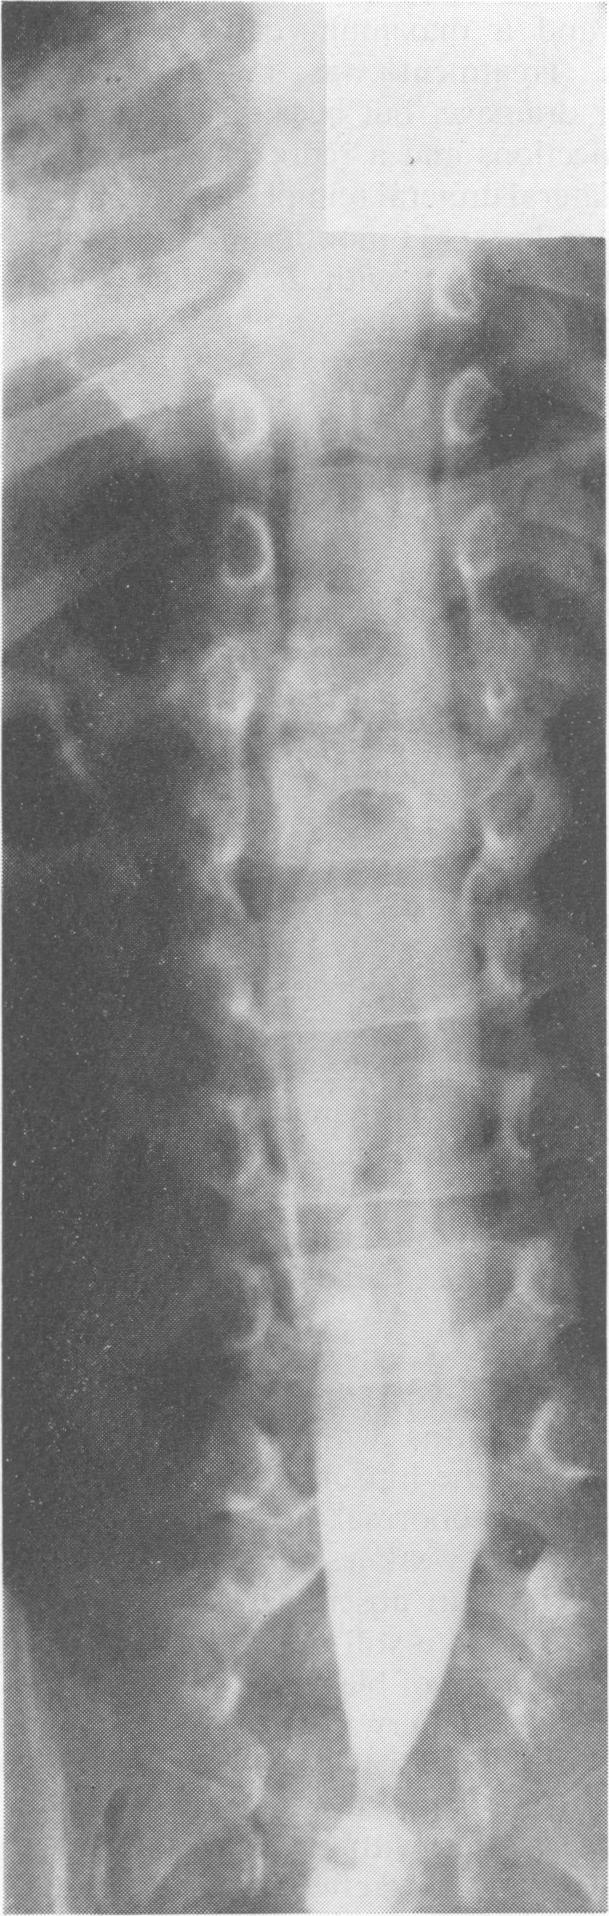

The association between spinal dysraphism and a neuropathic bladder is well known, but the diagnosis of the spinal lesion and the associated renal problems is often delayed. Four children referred with orthopaedic problems and in whom the bladder abnormally proved to be the major disability are described. Despite widely differing vertebral involvement, all had lower motor neurone neurological deficits confined to lumbar and upper sacral segments. All had unstable, variably thickened, small bladders, and it is proposed that the bladder abnormality is the result of a partial lesion of lumbosacral innervation, and not of an upper motor neurone lesion.

脊髓发育异常与神经源性膀胱之间的关联已为人熟知,但脊髓病变及相关肾脏问题的诊断常常延迟。本文描述了4例因骨科问题前来就诊的儿童,经证实膀胱异常是其主要致残因素。尽管椎体受累情况差异很大,但所有患儿均有局限于腰段和上骶段的下运动神经元神经功能缺损。所有患儿的膀胱均不稳定、厚度不一且较小,本文认为膀胱异常是腰骶部神经支配部分损伤的结果,而非上运动神经元损伤所致。